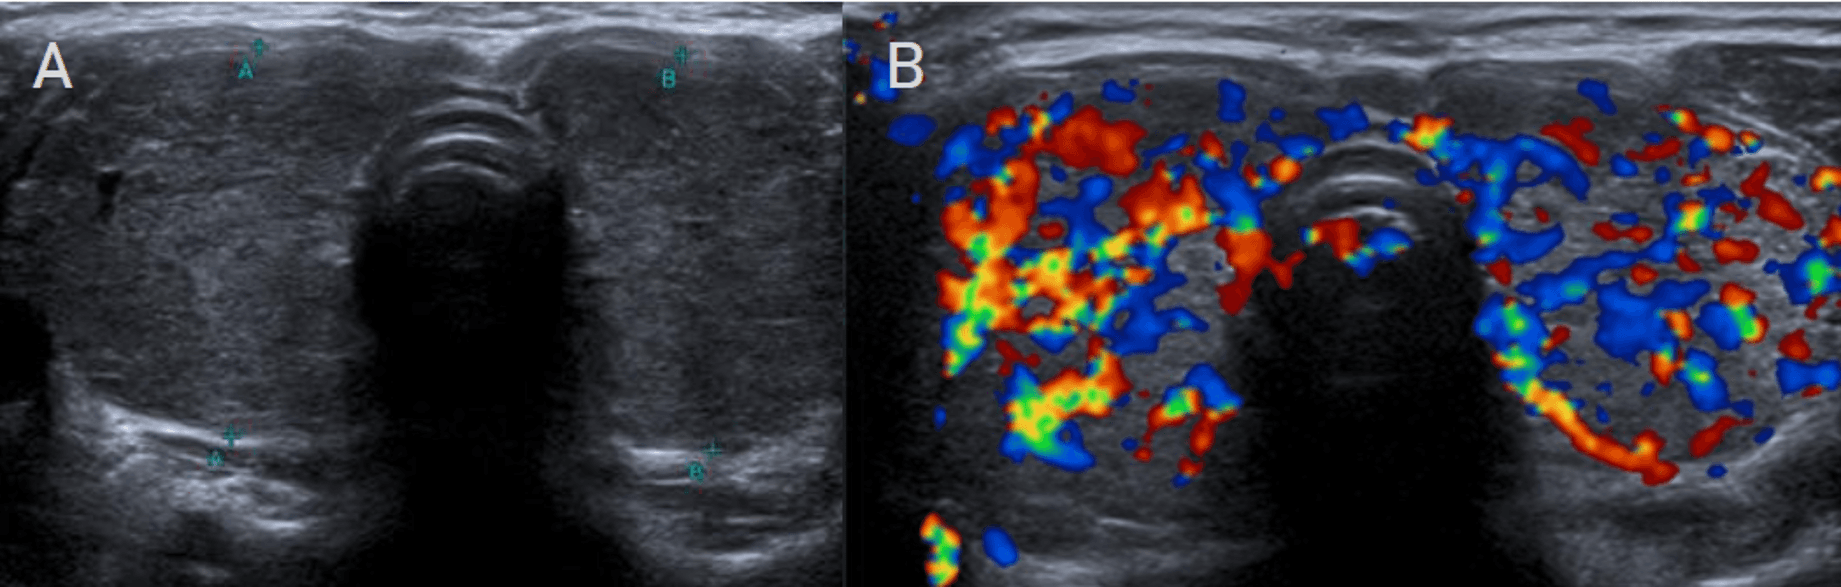

Cuando la clínica es ambigua, la ecografía con Doppler se convierte en la herramienta decisiva para distinguir las dos grandes entidades autoinmunes. En la tiroiditis de Hashimoto, el patrón clásico combina aumento difuso de la glándula, múltiples micronódulos hipoecogénicos rodeados por septos finos hiperecogénicos, conocido como patrón en jirafa, además de nódulos sólidos hiperecogénicos tipo white-knight. Aunque puede existir hipervascularización, las velocidades picosistólicas suelen mantenerse en rangos no francamente elevados. En la enfermedad de Graves-Basedow, en cambio, la firma diagnóstica es el infierno tiroideo: hipervascularización difusa y marcada, acompañada de velocidades picosistólicas claramente elevadas, en general por encima de 60 a 70 cm/s. La diferencia no es solo estética. Es hemodinámica, funcional y terapéutica.

La enfermedad de Graves-Basedow convierte la ecografía tiroidea en una lectura funcional de alta precisión. En esta imagen, el aumento difuso del volumen glandular y la heterogeneidad parenquimatosa encuentran su correlato decisivo en el Doppler color: una hipervascularización exuberante que configura el clásico infierno tiroideo. Para el radiólogo, este patrón no solo confirma actividad autoinmune; redefine el diagnóstico diferencial frente a otras tiroiditis difusas y subraya que, en tiroides, la hemodinámica puede ser tan determinante como la morfología.